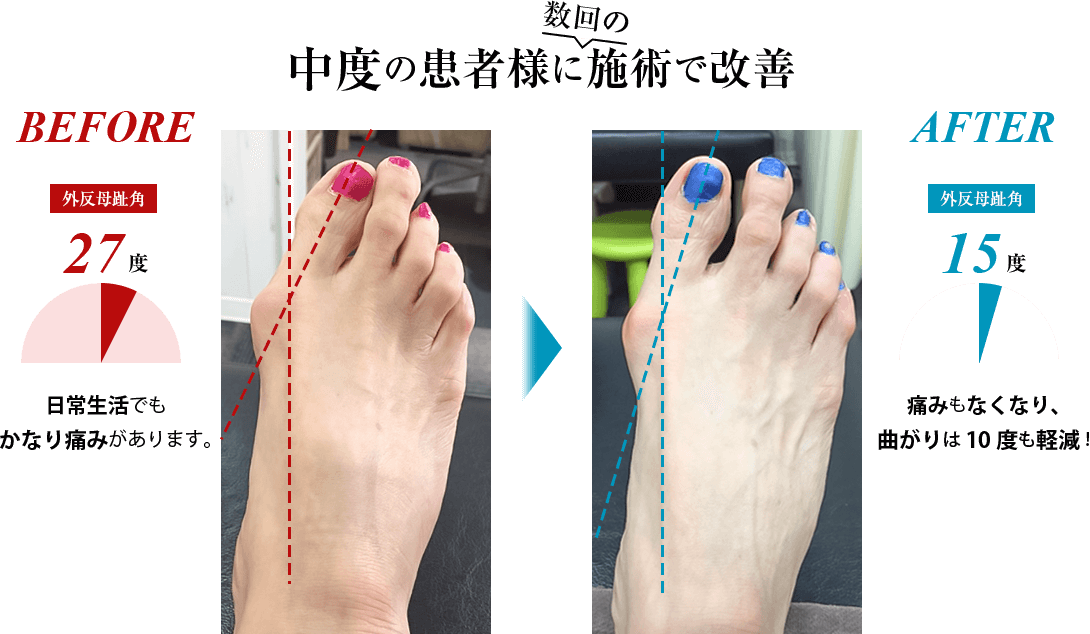

慢性的な膝や腰の痛み、頭痛、肩こり、外反母趾、骨盤の歪み、婦人科系疾患、慢性疲労、不眠、カラダのたるみ、便秘と多様な悩みに苦しむ方をこれまで施術してきましたが、どの方も共通していたのは「距骨」が歪んでいたことでした。 日常的な様々な痛みや症状の原因は、この土台である距骨にあるのです。

距骨を整える事により痛みの無い健康なカラダを取り戻して行きます。